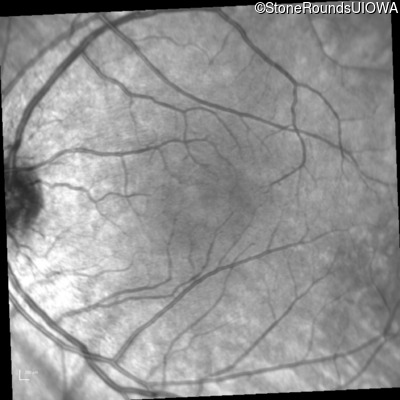

Infrared Fundus Photograph - Right - 20/25

Exemplar